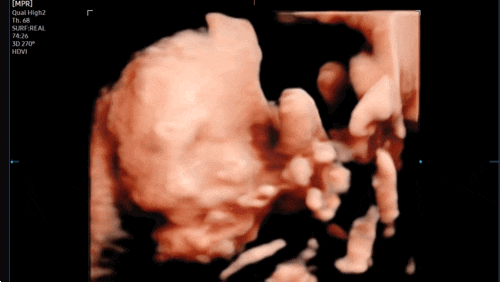

[임신 27주차] 증상, 입체초음파 성공! 극심한 관절통.. 황금기 끝난건가요?

?27주차 증상❤️ 1) 일이 많아 좀 돌아다니면 여지없이 허리랑 생리통배가 끊아지듯 아파서 식겁함ㅠㅠ...